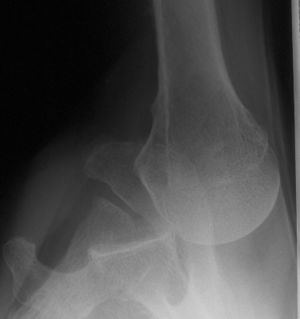

Axillary view

Recurrent/Congenital/Acquired

Bernageau view is the best to demonstrate posterior glenoid rim deficiency posterior subluxation and associated bone loss.